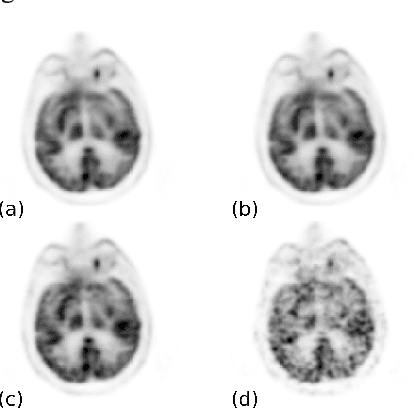

Abstract:Positron emission tomography (PET) is widely used in various clinical applications, including cancer diagnosis, heart disease and neuro disorders. The use of radioactive tracer in PET imaging raises concerns due to the risk of radiation exposure. To minimize this potential risk in PET imaging, efforts have been made to reduce the amount of radio-tracer usage. However, lowing dose results in low Signal-to-Noise-Ratio (SNR) and loss of information, both of which will heavily affect clinical diagnosis. Besides, the ill-conditioning of low-dose PET image reconstruction makes it a difficult problem for iterative reconstruction algorithms. Previous methods proposed are typically complicated and slow, yet still cannot yield satisfactory results at significantly low dose. Here, we propose a deep learning method to resolve this issue with an encoder-decoder residual deep network with concatenate skip connections. Experiments shows the proposed method can reconstruct low-dose PET image to a standard-dose quality with only two-hundredth dose. Different cost functions for training model are explored. Multi-slice input strategy is introduced to provide the network with more structural information and make it more robust to noise. Evaluation on ultra-low-dose clinical data shows that the proposed method can achieve better result than the state-of-the-art methods and reconstruct images with comparable quality using only 0.5% of the original regular dose.